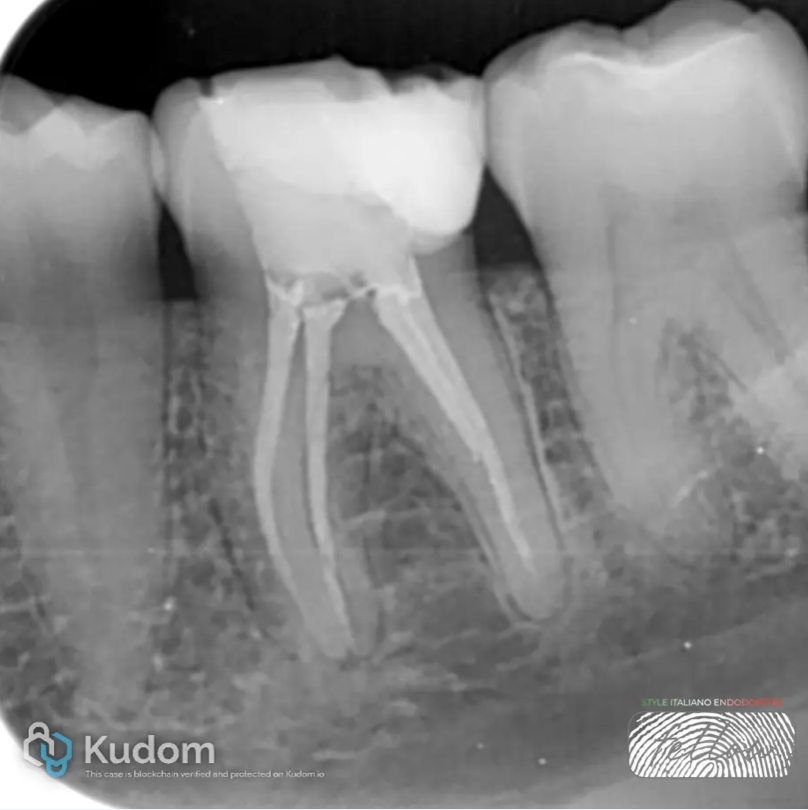

Fig. 4

Master Cone Fitting: The final working length of the three mesial and the distal canals was confirmed using a master cone.